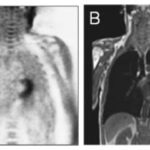

When can I go back to doing sports? Whoever it is, an amateur or professional athlete, hamstring injury is a very common situation and the question will be asked. Will you be able to answer it? Article: New MRI muscle classification systems and associations with...